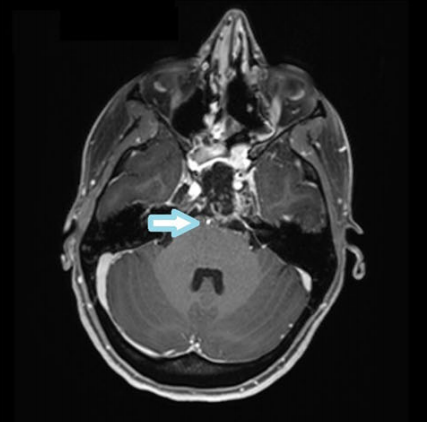

术后MRI显示近完全肿瘤切除(残留部分位于海绵窦水平)和通畅的血管(箭头所示)。